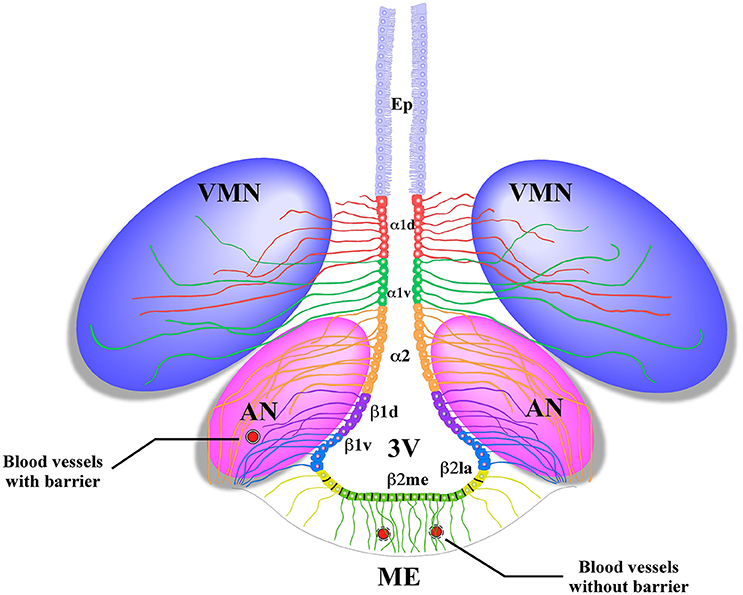

Как работает центр насыщения в гипоталамусе: визуальные иллюстрации